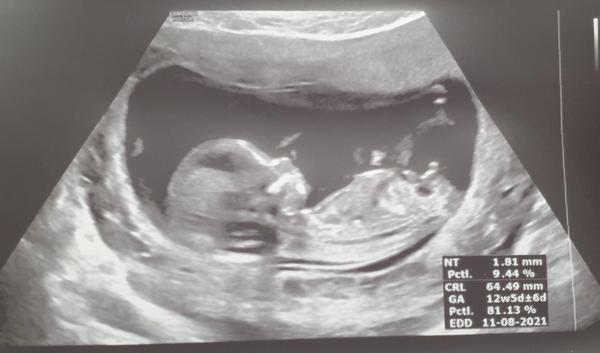

@mikejla_a doktor mi zatím nerekl nic, když jsme koukali poprve, tak ten hrbolek mířil uplne dolu a byl delsi až jsem se divila a pak na to koukal z jiného pohledu a vypadalo to jak na te fotce,tak už opravdu nevím. První fotka byla tato,ale to byl asi 11 tyden.

@kika115 tady jsem našla podobnou fotku a také to vypadá na kávové zrno a pri tom prvním screeningu vas řekli co? Ja jsem ted 15tt tak musím ještě počkat na dalsi fotecku.🙂

Holky, co myslíte? Kluk nebo holka? Když si odmyslím bambulku tak vidím kávové zrno. Vidíte ho taky?

Je možné aby byla bambulka pupečník nebo je to kluk jak buk? 🙂)